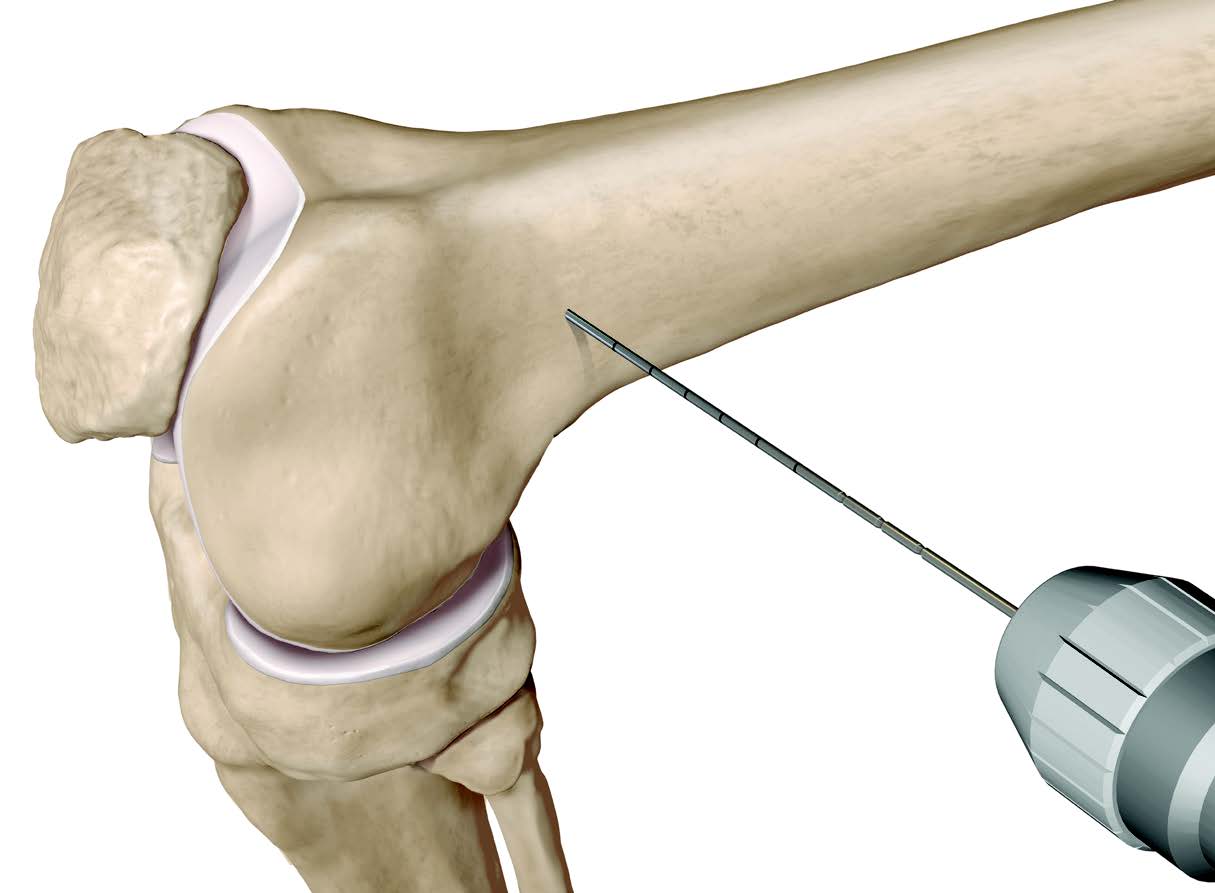

Osteotomy

- insert guide wires

- proximal lateral to distal medial

- proximal 1 - 2 cm above flare of lateral condyle

- aim towards adductor tubercle

- risk of medial hinge fracture reduced if osteotomy at or distal to adductor tubercle

- ensure these are perpendicular to the femoral shaft in the sagittal plane

- above patellofemoral joint and posterior condyles

- stop osteotomy 1 cm short of medial cortex